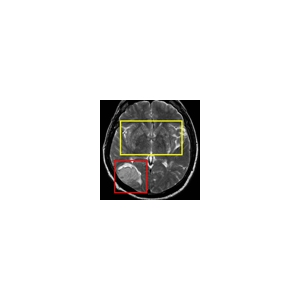

Bei der Tagung „Ictus", die am 28. Juni um 8.45 Uhr in der Europäischen Akademie Eurac in Bozen beginnt, setzen sich Fachleute aus den drei Ländern Tirol, Trient und Südtirol mit unterschiedlichen Fragen im Zusammenhang mit der Thematik Schlaganfall auseinander. Die neuesten Erkenntnisse zur Vorbeugung, Diagnose und Therapie stehen ebenso auf der Tagungsagenda, wie die territoriale Organisation und der Zugang zu den Leistungen, sowohl der Kardiologen, als auch der Neurologen und der Allgemeinmediziner. Bei der Tagung werden also nicht nur klinisch-wissenschaftliche, sondern auch gesundheitsökonomische, wie auch praktische Erkenntnisse für den Patienten und die betroffenen Familien aufzeigt. Organisiert wird die Tagung „Iktus" vom Landesamt für Krankenhäuser in der Landesabteilung Gesundheitswesen organisiert und vom Europäische Verbund für territoriale Zusammenarbeit (EVTZ) „Europaregion Tirol-Südtirol-Trentino".